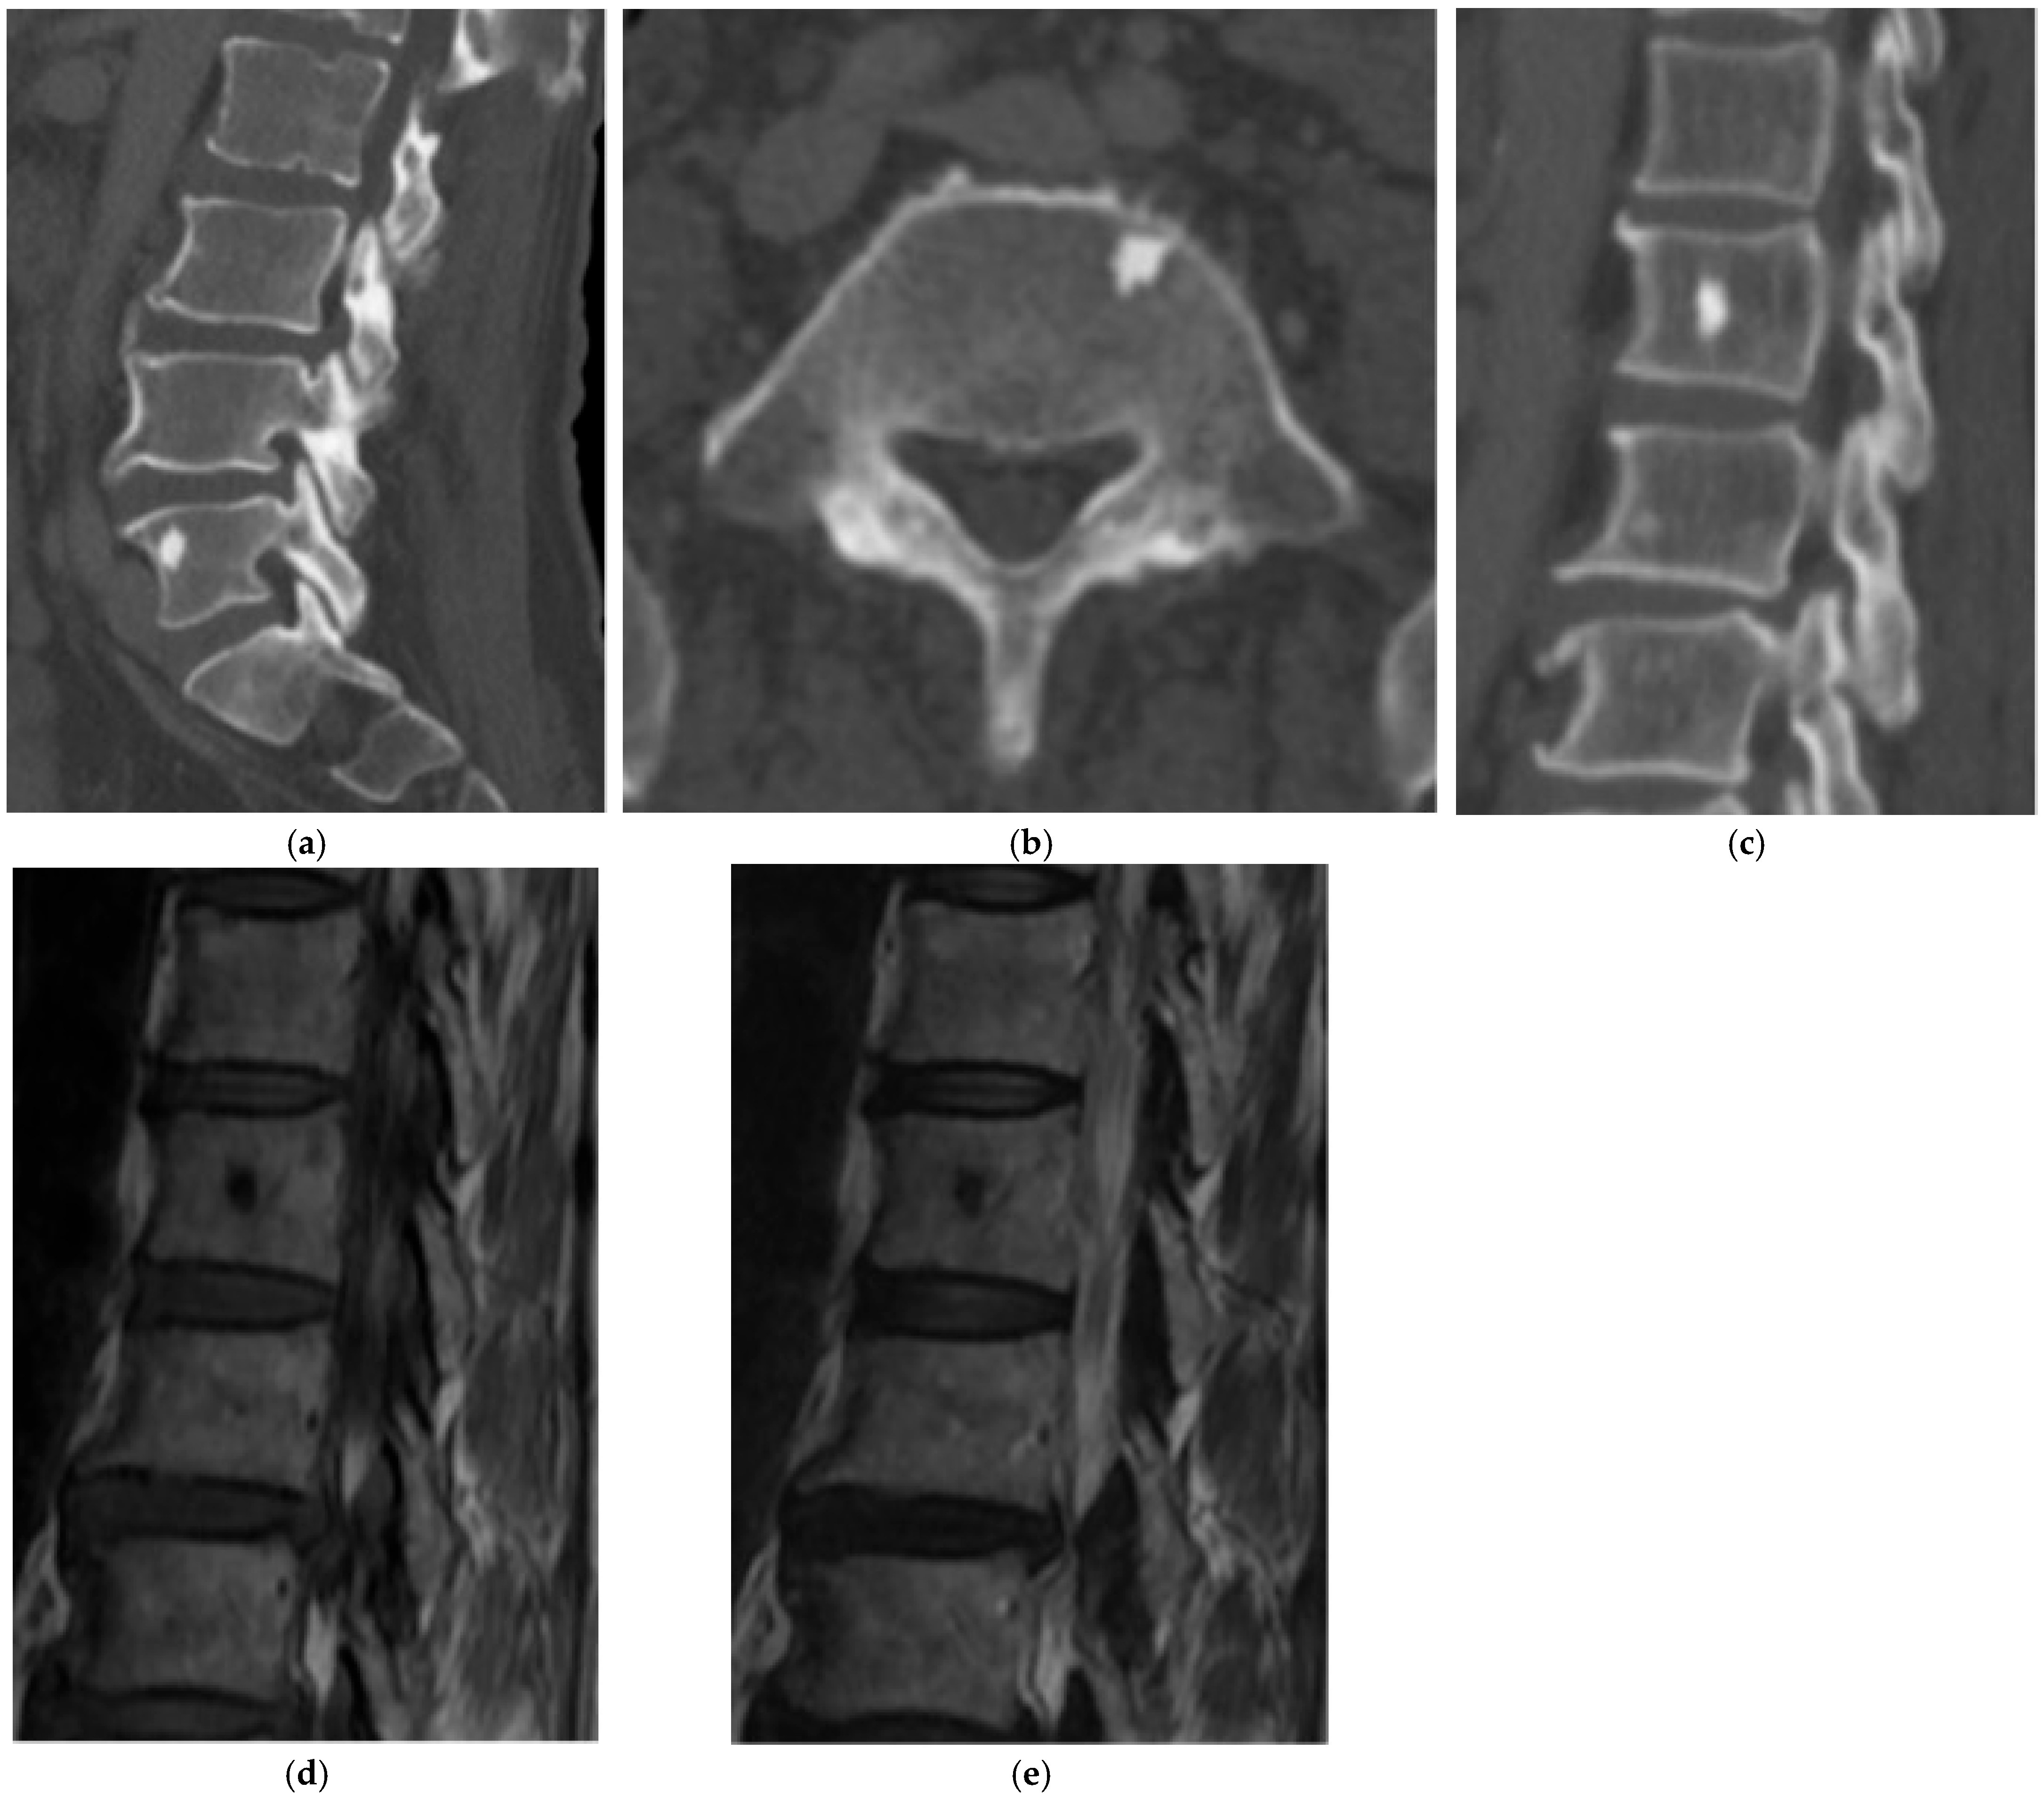

2.1.2. Osteoid Osteoma

2.1.3. Osteoblastoma